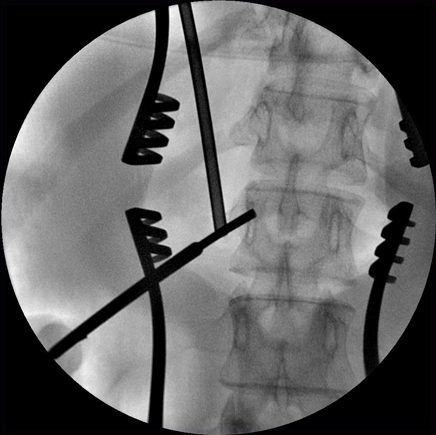

Передовые режимы визуализации для качественных изображений плотных структур

Необходимый уровень качества визуализации сложной анатомии обеспечивается также реализованными в аппарате BV Vectra режимами цифровой экспозиции и рентгеноскопии высокого разрешения. Для быстрого переключения этих режимов достаточно нажать педаль или кнопку ручного переключателя.